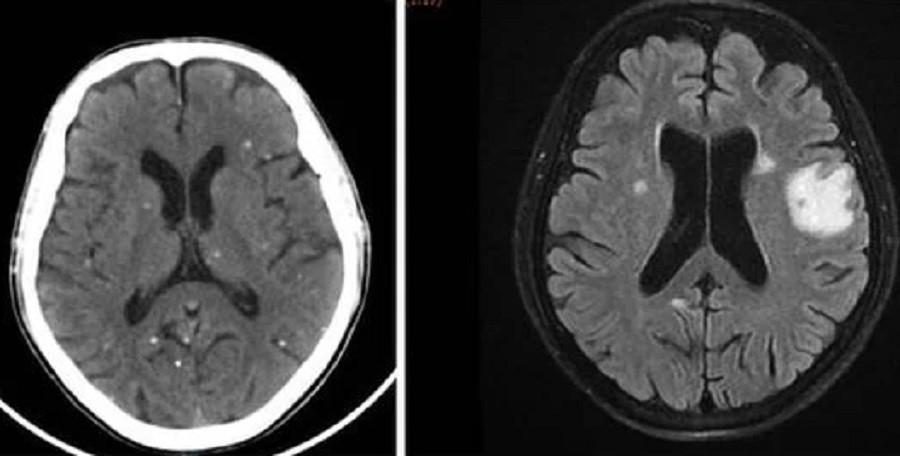

Nang sán dải ký sinh ở bán cầu não hai bên là nguyên nhân khiến người bệnh bị tổn thương não, biểu hiện như đột quỵ |

TS.BS Trần Thanh Hùng, Phó khoa Nội Thần kinh Tổng quát, Bệnh viện Nhân Dân 115 cho biết, qua thăm khám và chẩn đoán hình ảnh ghi nhận, người bệnh có tổn thương não nhiều vị trí, phù não. Kết quả xét nghiệm huyết thanh học cho thấy, bệnh nhân dương tính với ấu trùng sán dải lợn (Cysticercus).

Trên kết quả X-quang và CT-Scan toàn thân, bác sĩ phát hiện bệnh nhân có vô số nang sán dải còn sống hoặc đã bị vôi hóa ở não, nhu mô phổi, trong da, cơ trên toàn bộ cơ thể. Qua điều tra dịch tễ, bác sĩ ghi nhận bệnh nhân có thói quen hay ăn gỏi thịt lợn tái sống và uống nước không đun sôi trong nhiều năm.